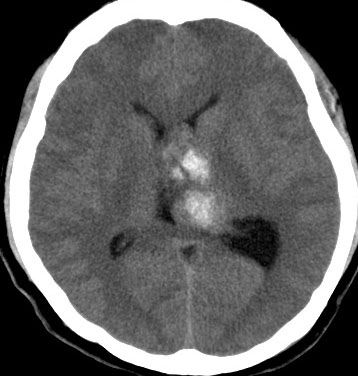

20代の男性の神経細胞腫です。側脳室の中のとても大きな腫瘍です。上段はガドリニウムという造影剤を入れた時のMRIです。下段の中央はCTですが,石灰化が見られます。脳外科の先生には,この脳室内腫瘍は一見transcallosal approach(経脳梁到達法)という手術で取れるように見えるかもしれませんが,そうではなくて,脳室の壁とくに上壁と側壁にくっついているのでなかなか取れません。この患者さんの場合は右の頭頂葉というところからtranscortical approach(経皮質到達法)で全摘出しました。後遺症もなく再発もなく術後10年が過ぎています。全部とれれば治ってしまう腫瘍です。